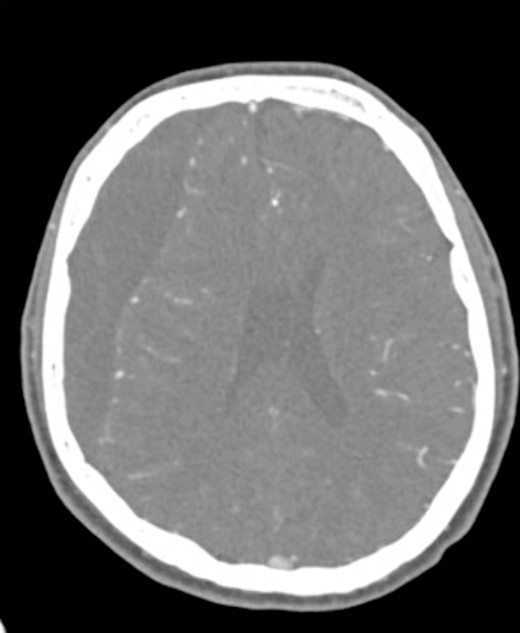

A 60-year-old male with cSDH presented to a Level I trauma center with lethargy, headaches, and left-sided hemiparesis. CT demonstrated thickened membranes and midline shift (Fig. 1).

An AR system was used to register the patient’s 3D anatomy onto the patients’ head (Fig. 2). Burr hole locations were annotated onto the registered 3D model to assist with craniotomy planning. Visualization of the 3D model confirmed plans for safe burr hole placement away from the dural venous and bony sinuses for a right frontoparietotemporal craniotomy. The AR headset was used once again to visualize the hematoma, vascular structures, and to confirm proper burr hole locations. The evacuation of the subdural hematoma was performed. Eight burr holes were placed, and a 14 × 11 cm bone flap was elevated to access the dura. The dura was then opened in a curvilinear fashion and hinged over the superior sagittal sinus. The cSDH was identified by its thick parietal and visceral membranes and underlying liquefaction, and these anatomic layers correlated directly with the AR overlay. The membranes of the hematoma were resected with the cortex demonstrating no gross abnormalities. The wound was irrigated, and the dura was closed primarily. The bone flap was then secured with two central tack-up structures followed by titanium reconstruction with multiple burr hole covers. There were no intraoperative complications, and the patient tolerated the procedure well with improved strength and decreased headache postoperatively. Post-operative CT showed interval decrease in the mixed-density subdural collection and reduced midline shift (Fig. 3).